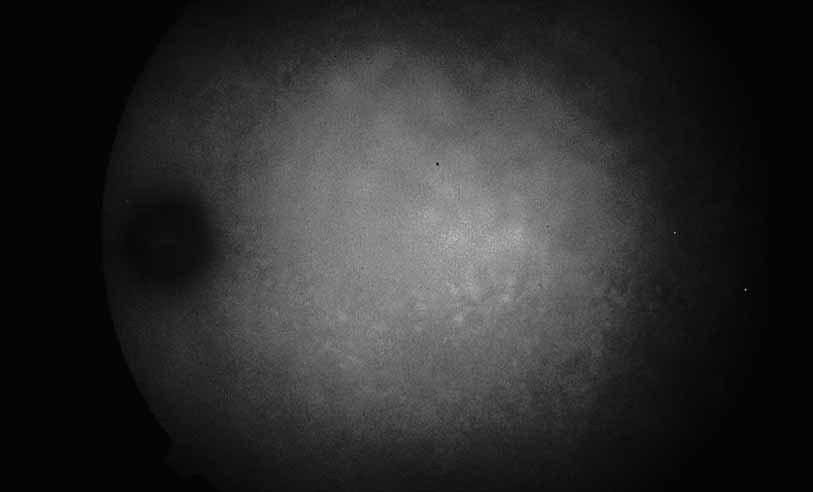

Fig. 10 Acute multifocal hemorrhagic retinal vasculitis. A middle-aged man presented with the picture of multiple branch vein obstructions and low-grade intraocular inflammation.

Fig. 11 Acute multifocal hemorrhagic retinal vasculitis. Fluorescein angiogram confirms the presence of associated retinal capillary non-perfusion without neovascularization at the onset of the disease.